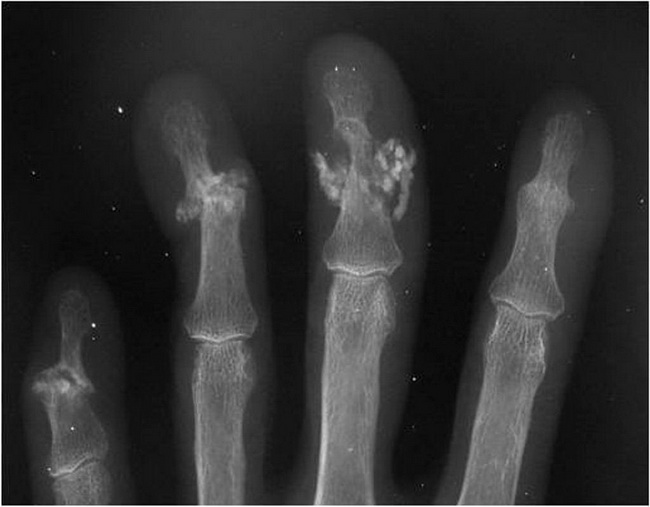

Subchondral sclerosis is a thickening of bone that happens in joints affected by osteoarthritis. If you’ve been diagnosed with osteoarthritis or have early symptoms of osteoarthritis, your doctor may mention subchondral sclerosis as one sign of the disease. “Subchondral bone” is bone that sits underneath cartilage in a joint.

Subchondral bone is found in large joints like the knees and hips, as well as in small joints like those of the hands and feet. “Sclerosis” refers to an unusual increase in the density or hardness of a tissue in the body.

Doctors can diagnose osteoarthritis without any signs of subchondral sclerosis. But when it’s present, the thickening of bone can help them diagnose osteoarthritis. Other conditions that have similar symptoms to osteoarthritis, such as rheumatoid arthritis, don’t lead to subchrondral sclerosis.

Overview. Subchondral sclerosis is the hardening of the bone just below the cartilage surface. It shows up in the later stages of osteoarthritis. Subchondral sclerosis is common in the bones found at the load-bearing joints, such as knees and hips. Other joints can be affected, including the hand, foot, or spine.

It can only be detected by X-ray or MRI. Subchondral sclerosis may not increase the risk of cartilage loss in your joint. In fact, a 2014 study suggests that it may be protective against cartilage loss and narrowing of the space in your joint.

Subchondral sclerosis , which is also called marginal sclerosis, is a thickening of the bone beneath the cartilage in joints. It can be associated with painful joint symptoms and bone spurs. Subchondral sclerosis is commonly seen in joints of the knee, hip, spine, and foot. Subchondral sclerosis, like bone spurs and cartilage loss, is a feature of osteoarthritis